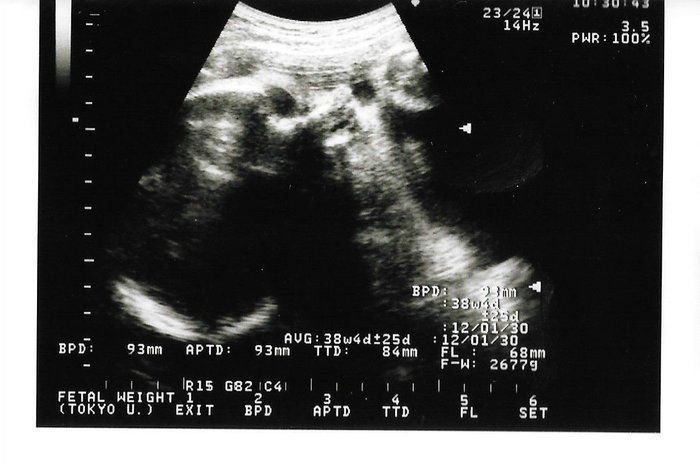

「背骨!足骨!ホントに人間がいる!」エコー画像を見る度、ゆっくり親になっていく私たち -

宝物の息子とはおなかのなかで対面してた!エコー写真で出会いからこれまでを振り返る -